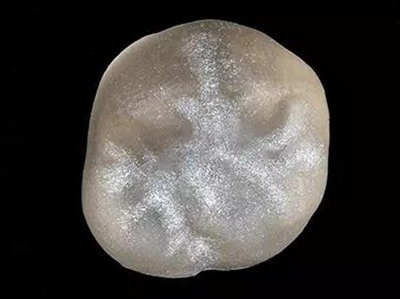

16牙位牙齒牙合面觀.

牙齒經(jīng)過根管治療且充填修補,需要重新修復。